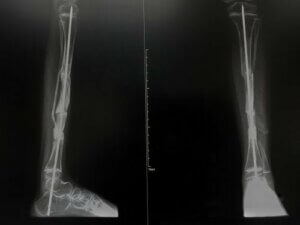

This type of osteogenesis imperfecta is considered the most serious. In fact, on many occasions, it can be fatal. This type is also divided into three groups, depending on the radiological characteristics.

The first is group II A, which is usually the most common and results in short bones, long bones, accordion tibia and rachitic rosary in the ribs. On the other hand, type II B also produces short, long, wide and wrinkled bones, but there’s no rachitic rosary in the ribs. Rib fractures may occur.